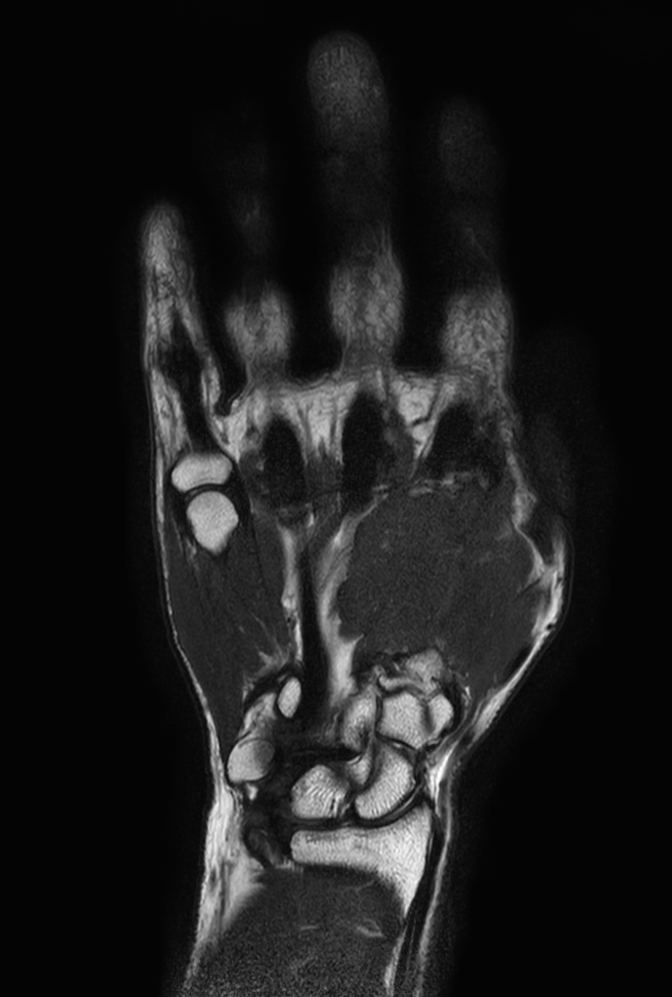

Coronal T1w TSE

-

Coronal T1w TSE mDIXON XD (In Phase)